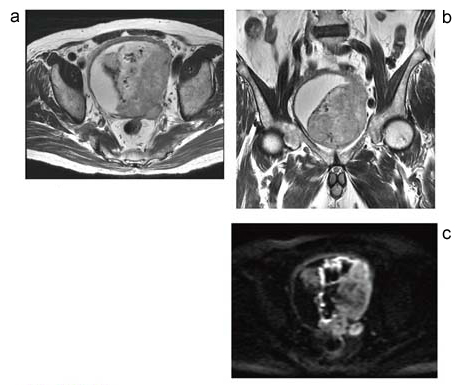

図7 膀胱がん

a:FSE法T2強調画像横断像 /

b:FSE法T2強調画像冠状断像 /

c:呼吸同期 DWI (b値800)

膀胱左側を占める腫瘍。膀胱筋層を越えて周囲脂肪組織へ浸潤する。T2強調画像(a,b)では,膀胱内の尿を含めて,信号は全体に均一に認められる。